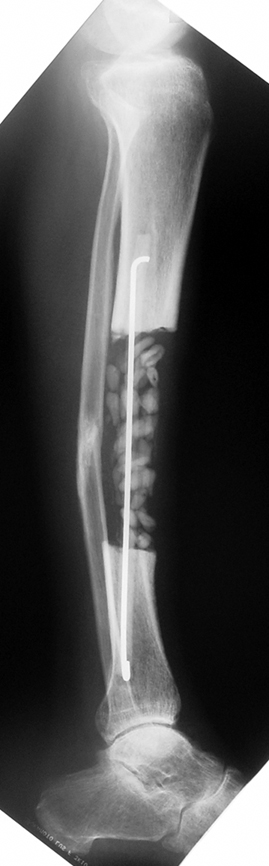

The duration of external fixation (external fixation index) depends on the amount of distraction required, and the extremity is prone to complications during this period. After the distraction phase is completed, the external fixator remains in place during the consolidation phase, which lasts twice as long as the distraction phase; but this period is hardly tolerated. If the external fixator is removed before sufficient consolidation is achieved, fractures, deformity and shortness will be the result. In our department, ‘lenghthening over nail’ method is used in order to decrease the external fixation index and increase patient comfort and activity level. In this method, the intramedullary nail is statically locked after the completion of the distraction phase, and external fixator is removed. The extremity is stabilized by the intramedullary nail during consolidation phase. In this way, complications due to long external fixation index or early removal of the external fixator are avoided.